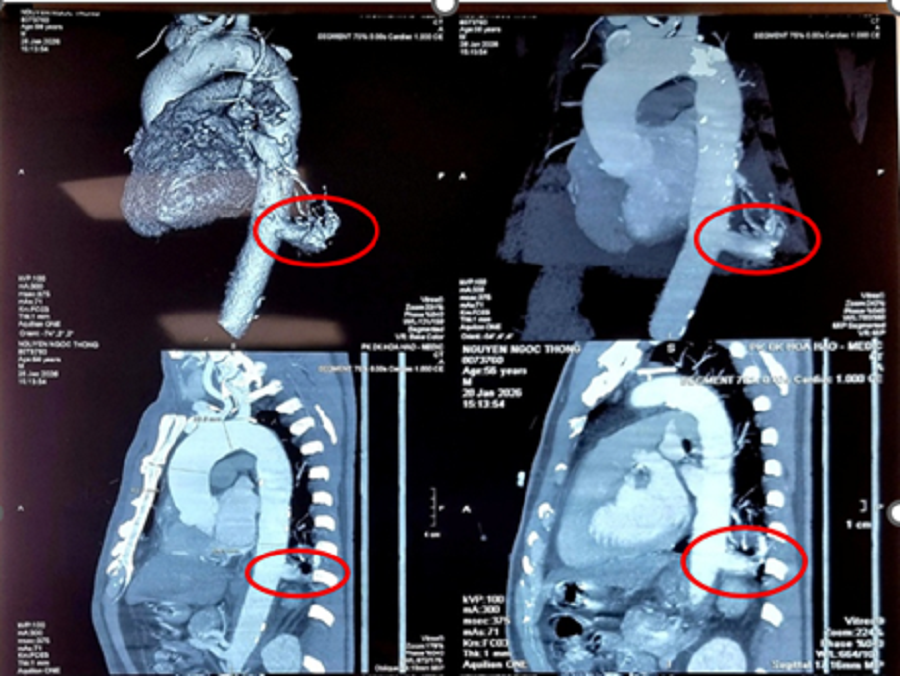

hinh-msct-nguc-1.png

Qua hình ảnh kiểm tra các bác sĩ ghi nhận tình trạng dị dạng bẩm sinh phổi biệt lập nội thùy ở người bệnh